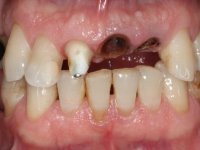

Patient male, 60 years old, non-smoker. After imaging and clinical examination, it was found that the patient had teeth 2.1 and 2.2 with extensive acrylic restorations, with screwed intra radicular posts and very poor endodontic treatments. Tooth 2.2 had an extensive apical lesion, the post had been placed on a false route and had mobility. Tooth 1.1 had an extensive resine restoration and tooth 1.2 presented a mesial restoration, also in composite resin, Class III type. The antero-superior sector was vestibularized, as consequence of a loss of vertical occlusion dimension associated with posterior edentulism. The patient showed reasonable periodontal health and satisfactory oral hygiene.